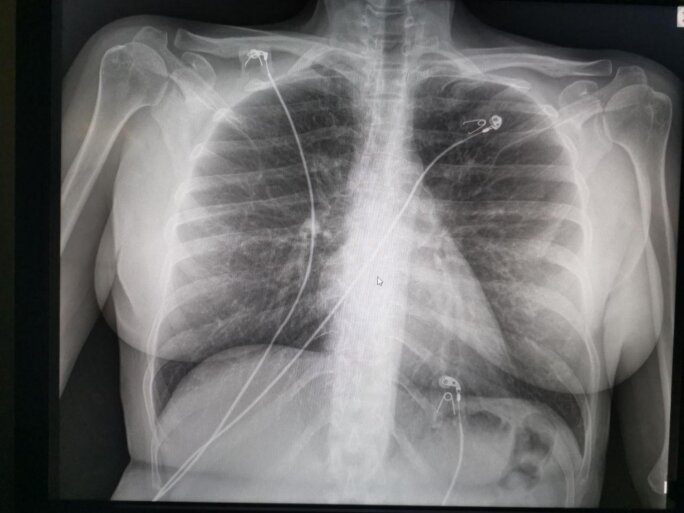

C’est harassant mais je ne me plaint pas, mes collègues en ont pour des heures comme ça…avant de sortir de la réa, Nathalie me demande si je veux des yaourts ? – Mais qu’est-ce que vous avez avec les yaourts aujourd’hui ? – c’est quelqu’un qui a fait un don…- oui je sais Nathalie, y’a du riz au lait ? – oui je crois – garde moi un pot alors stp…J’ai gagné ma journée en pot de riz au lait et ça me fait sourire. Je checke les radios avant de les ramener à Marcel. Certaines sont quasiment normales, d’autres présentent des tableaux de pneumopathies ou de fibroses interstitielles diffuses...

Agrandissement : Illustration 5